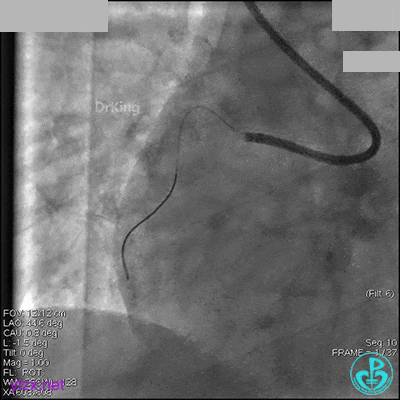

1周后再次上台,右冠脉3级血流,3段局限性严重狭窄,内膜模糊,应该是上次操作夹层遗留下的血肿。

先处理前降支开口严重狭窄并顺利植入前降支到左主干支架。